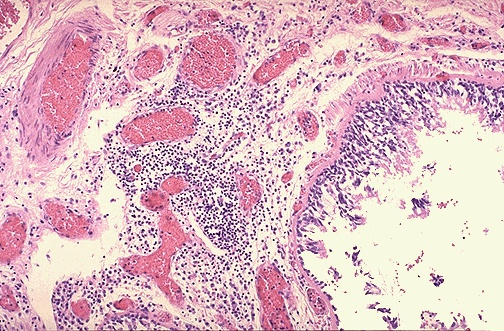

| This photomicrograph shows a bronchus with increased numbers of chronic inflammatory cells in the submucosa. Chronic bronchitis does not have characteristic pathologic findings, but is defined clinically as a persistent productive cough for at least three consecutive months in at least two consecutive years. Most patients are smokers. Often, there are features of emphysema as well. |